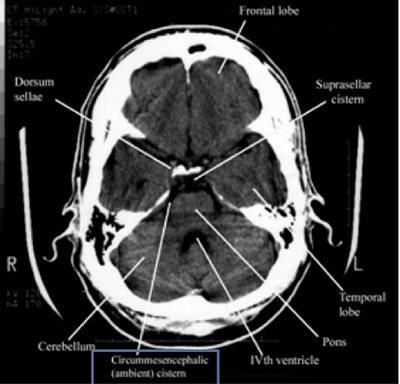

Step 2: Cisterns

Cisterns

Cisterns are the compartments within any of the openings in the subarachnoid space of the brain filled with cerebrospinal fluid. Two key questions to answer regarding the four key cisterns (Circummesencephalic, Suprasellar, Quadrigeminal and Sylvian)

• Is there blood?

• Are the cisterns open?